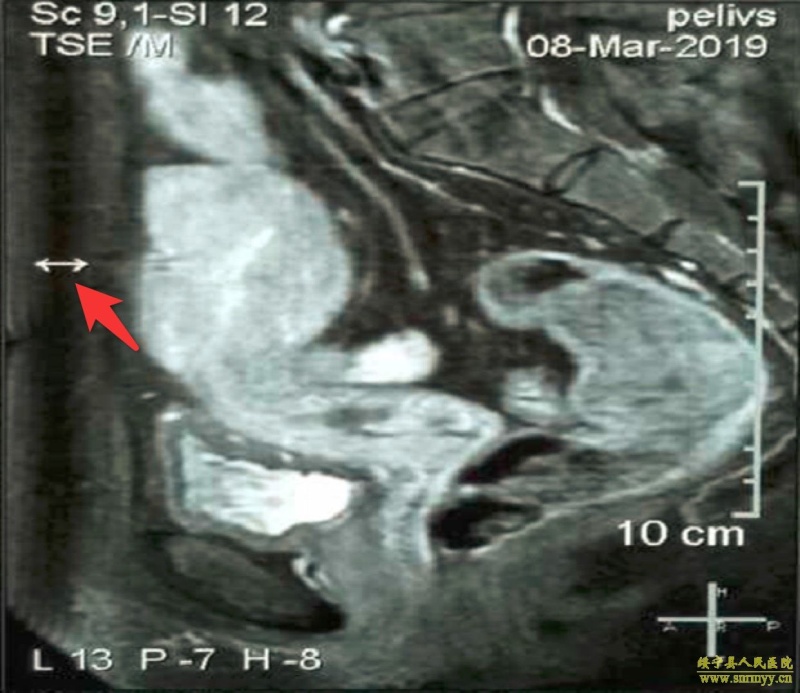

术前进一步完善了盆腔MRI、双下肢血管彩超及D-二聚体等检查,MRI提示子宫与腹壁紧密粘连,但未见明显增大淋巴结,D-二聚体3.10mg/L,但双下肢血管彩超未见异常,考虑患者血栓高危,术前予低分子肝素预防性抗凝。考虑患者多次手术史,MRI提示子宫与腹壁紧密粘连,经过充分术前准备后在全麻下行剖腹全子宫双附件切除+盆腔粘连松解术,进腹后留取腹腔冲洗液送快速病检,正如术前评估一样,子宫前壁与盆腹壁、大网膜、肠道、膀胱等致密粘连,湘雅医院妇科专家江春博士、绥宁县人民医院妇科主任罗雪花副主任医师及副主任黄芬主治医师、周水英主治医师配合下,小心分离粘连,高位结扎切断双侧卵巢血管并切除子宫,剖视子宫,进一步探查盆腹腔未扪及肿大淋巴结,顺利完成手术。

图一 箭头“←→”提示子宫与腹壁精密粘连